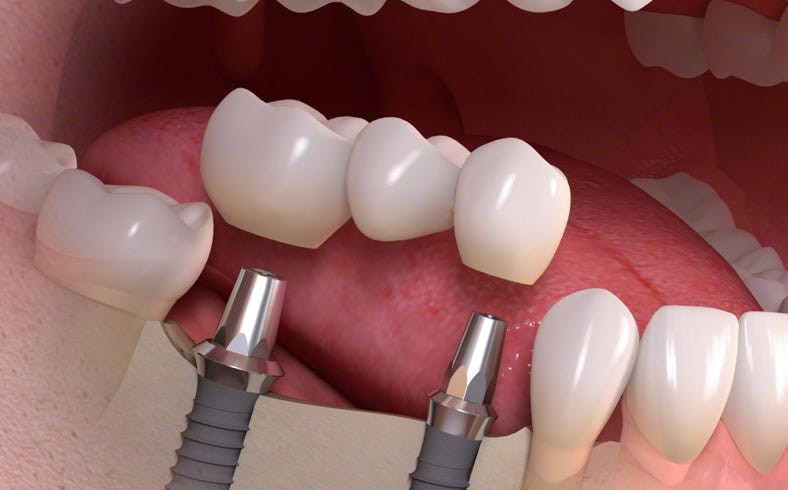

Wenn ein Zahn und seine Wurzel fehlen, ist die langfristige Lösung für eine natürliche Funktion ein Dentalimplantat mit dazu passender Krone.

Über Zahnimplantate

Ein Dentalimplantat ist ein kleiner, aber stabiler Pfosten aus biokompatiblen Metallen oder Keramiken. Es wird unter Lokalanästhesie anstelle der fehlenden Zahnwurzel in den Kieferknochen gesetzt und fungiert als Stütze für den Zahn.

Die Einheilphase dauert zwischen 6 und 12 Wochen, abhängig von der individuellen medizinischen Situation. Während dieses Zeitraums wird das Implantat sicher im Kieferknochen befestigt – ein als Osseointegration bezeichneter Prozess. Nach der Einheilung fungiert diese künstliche Wurzel als Basis für die Befestigung einzelner Kronen, mehrgliedriger Brücken oder einer Totalprothese.